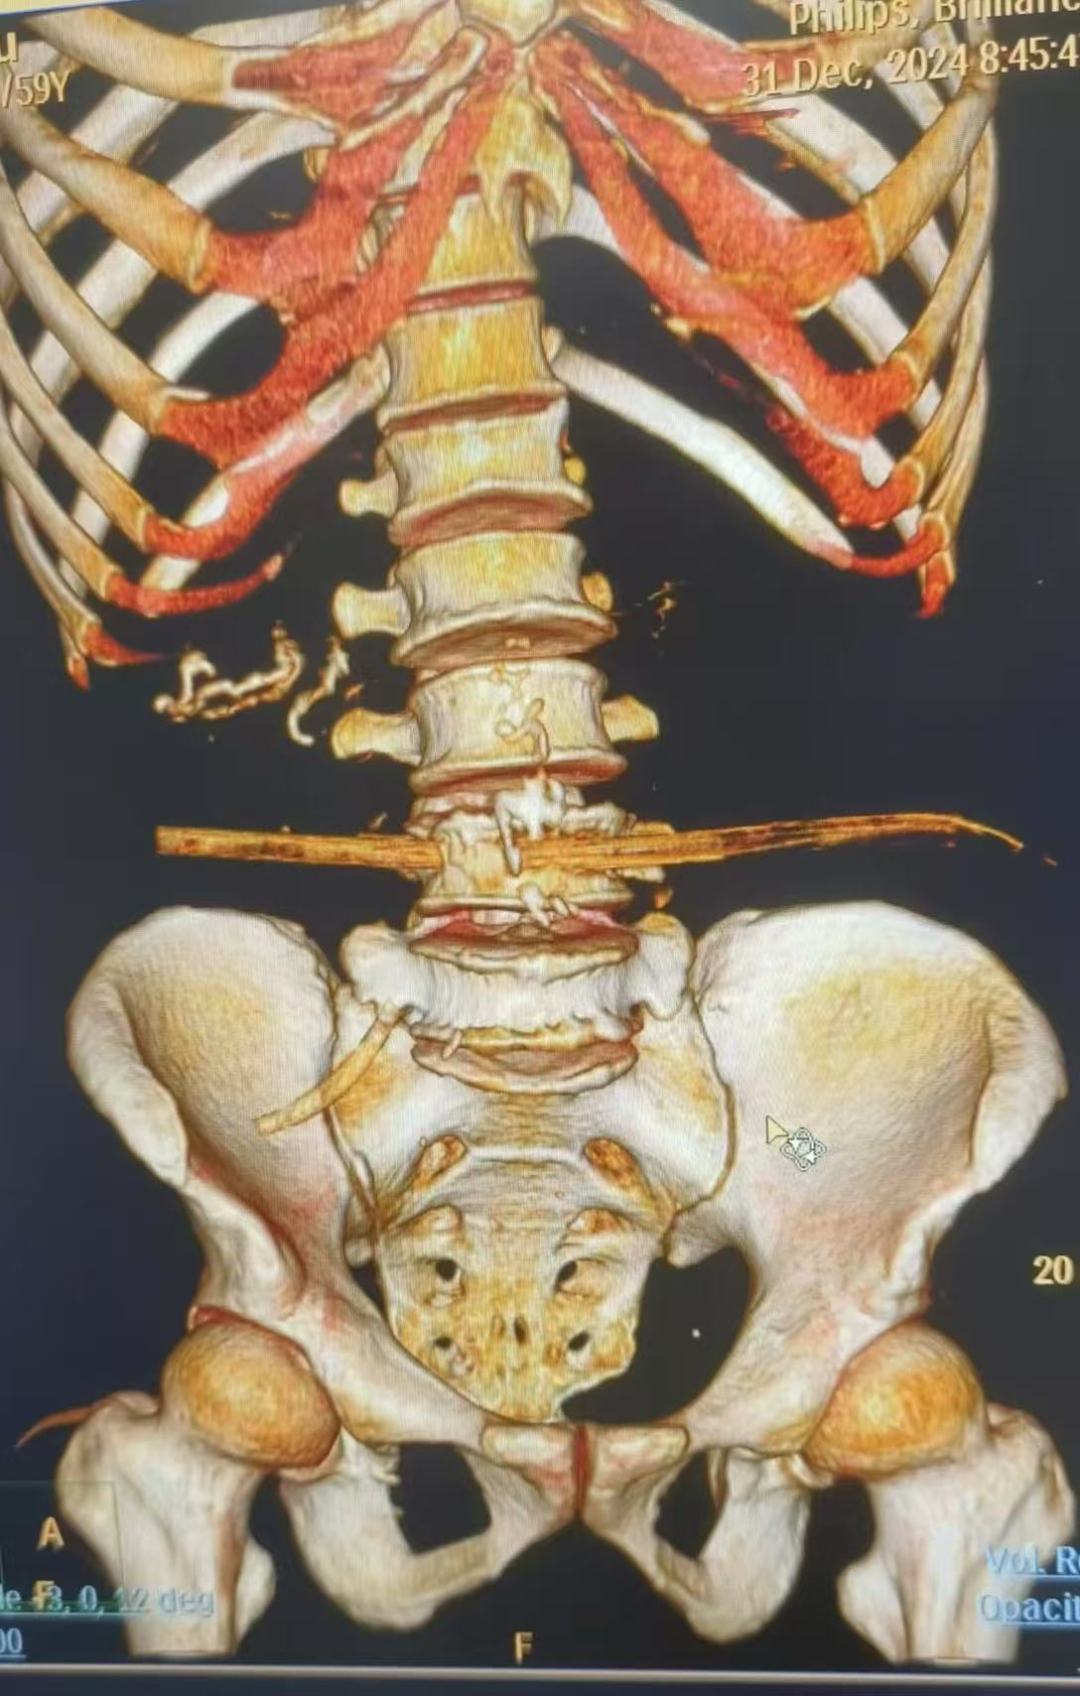

据了解,患者59岁,受伤1小时入院,入院后下肢活动及感觉正常,心率、血压及氧饱和度尚正常,腰部俨然可见一根直径约3厘米的木棍刺入,横穿腹部,另一端到达左侧腰部皮下。患者到达急诊科后,医护人员立即给予监护、吸氧、开放静脉通道、补液处理,普通外科、泌尿外科、骨科等相关科室迅速会诊、完善腹部CT检查及三维重建。CT影像结果显示,木棍经右侧腰部刺入腹部,横穿升结肠、腰大肌及L4椎体达到左侧腹部皮下,降结肠损伤待排。万幸的是木棍避开了重要的血管、神经、肝及肾脾。